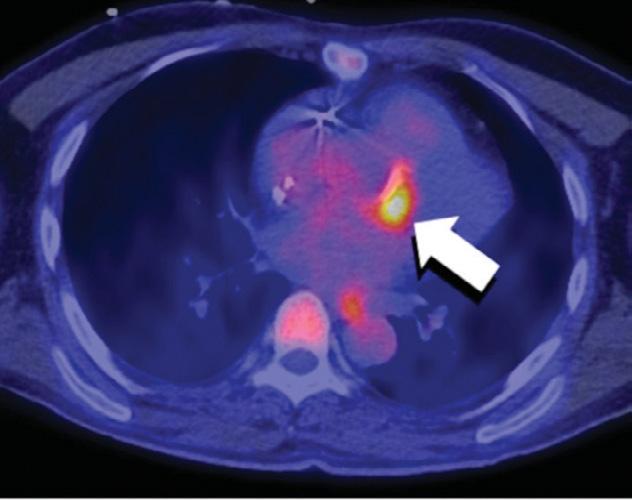

5. Évaluation de l’endocardite : il s’agit d’une maladie qui se caractérise par une inflammation de la paroi interne du cœur, y compris les valves, en raison d’une infection (figure 3). L’infection peut entraîner la formation d’amas de bactéries et de cellules sanguines, appelés végétations, sur les valves cardiaques. Ces végétations peuvent endommager les valves et entraîner des complications comme une insuffisance cardiaque, un accident vasculaire cérébral et une septicémie. La TEP-FDG peut être utilisée pour détecter une infection des valves cardiaques, mais également pour surveiller l’évolution de l’endocardite ainsi que l’efficacité du traitement. L’examen peut aider à identifier une rechute précoce de la maladie et à évaluer la nécessité de modifier les plans de traitement.

Figure 3 : La TEP-FDG est particulièrement utile pour l’évaluation de l’endocardite sur prothèse valvulaire. Chez cette personne qui possède une prothèse de valve aortique, une zone importante d’absorption indique la présence d’une infection active.